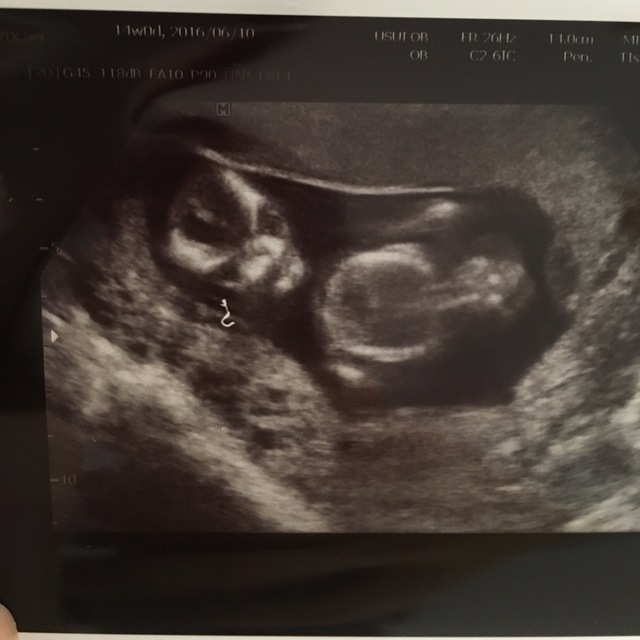

14週0日(14w0d・女の子)|62ki さん(24歳)

エコー写真撮影時のエピソード:

この子の前に一度授かった時は、同じ週数の時に前回の検診では確認できた心拍が確認出来ず流産をしていました。

今回も流産してしまったら…と不安いっぱいの中、元気な姿を見せてくれて喜びでエコーを見ながら涙した事を今でも覚えています。

吐き悪阻で凄く大変だったけど、この時は気持ち悪いことも忘れていました(笑)